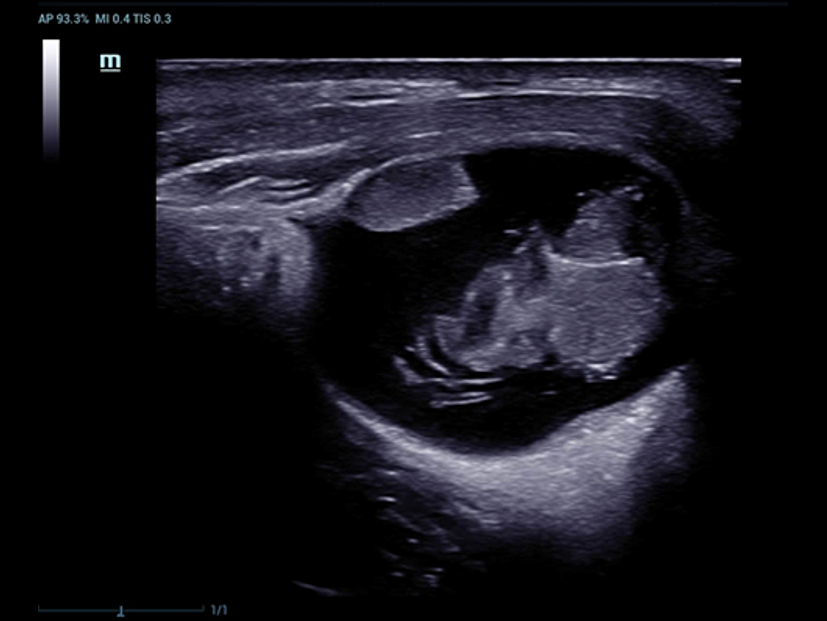

Trauma della caviglia